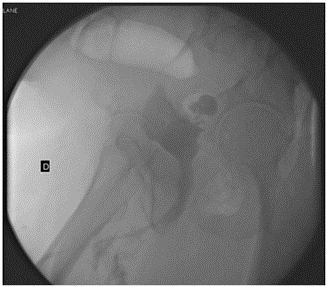

A 67-year-old male patient with a medical history of diabetes mellitus, chronic renal failure and dyslipidemia consults for urinary discomfort associated with a perineal abscess. The physical examination reveals a fluctuating perineal tumor that spontaneously drains purulent content through the skin. The cystography shows a contrast extravasation at the level of the bulbar urethra compatible with the urethral fistula (Figure 1), and the endoscopic examination shows a devitalized bulbar urethra with a stenotic area that prevents the endoscope from passing. During the exploration, abundant saline solution was observed through the perineum. Surgical drainage of the collection was performed as well as the placement of a bladder and suprapubic catheter. The patient presented recurrence of the collection in the first month of follow-up, so it was decided to perform a new drainage of the abscess and a Friedrich of the perineal wound. The anatomopathological outcomes of the latter revealed the existence of a well-differentiated squamous cell carcinoma in areas of abundant keratinization that widely infiltrate the skin and soft tissue.

Figure 1: Cystography shows a small capacity bladder with irregular borders. Contrast extravasation is evident at the level of the middle bulbar urethra.